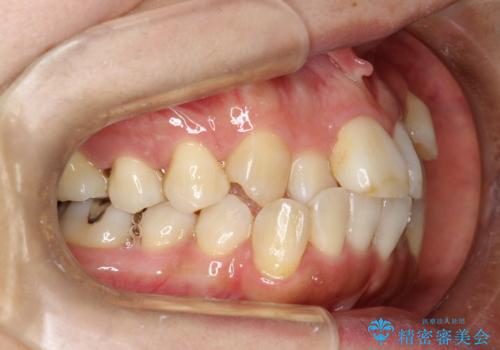

プラーク(細菌の塊)や歯石がたまると歯の表面はザラつきいてきます。そのザラつきは歯周病や虫歯菌の棲家となります。そのまま放置すると、歯肉が腫れてきたり、歯肉から出血したり、口臭が強くでたりします。とくに歯肉の境目は、歯磨きで汚れを除去することが難しく、プラーク(細菌の塊)や歯石が溜まりやすい場所です。

歯並が、がたついている場合はなおさら汚れが溜まりやすいです。矯正治療前や矯正中、定期的にPMTCをすることで、矯正治療中の歯肉トラブルを防ぐことにつながります。